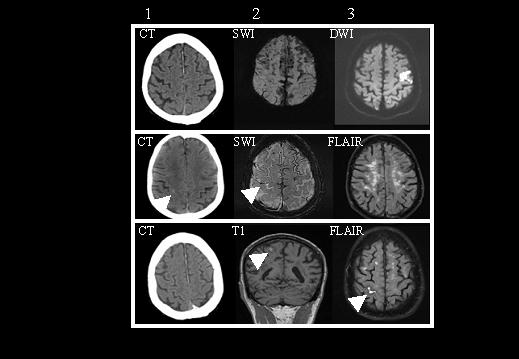

Introducción. La angiopatía amiloide cerebral (AAC) se caracteriza por el depósito de β-amiloide en la pared de las arterias de pequeño y mediano calibre de la corteza cerebral y leptomeninges. La sintomatología puede incluir eventos transitorios de diverso origen, pudiendo ser difícil el diagnóstico diferencial en el momento agudo. Caso clínico. Paciente con antecedente de ictus isquémico, que presentó crisis somestésicas secundarias a microsangrado cerebral por AAC que simulaban ataques isquémicos transitorios. Se redujo la medicación antiagregante y posteriormente se inició tratamiento antiepiléptico desapareciendo los episodios. Las secuencias de susceptibilidad paramagnética en Resonancia Magnética cerebral fueron de gran utilidad para el diagnóstico (SWI-RM). Conclusiones. Los microsangrados de la AAC pueden manifestarse en forma de crisis, simulando déficits focales sensitivos transitorios que pueden ser atribuidos erróneamente a isquemia cerebral. Este caso sugiere que, incluso si existe historia de accidentes cerebrovasculares isquémicos, deberían considerarse microsangrados por AAC como causa posible de pseudoaccidentes isquémicos transitorios. Las secuencias SWI-RM pueden ser útiles para identificarlos. De este modo puede prevenirse el inicio o escalada del tratamiento antiagregante o anticoagulante, evitando complicaciones potencialmente devastadoras.